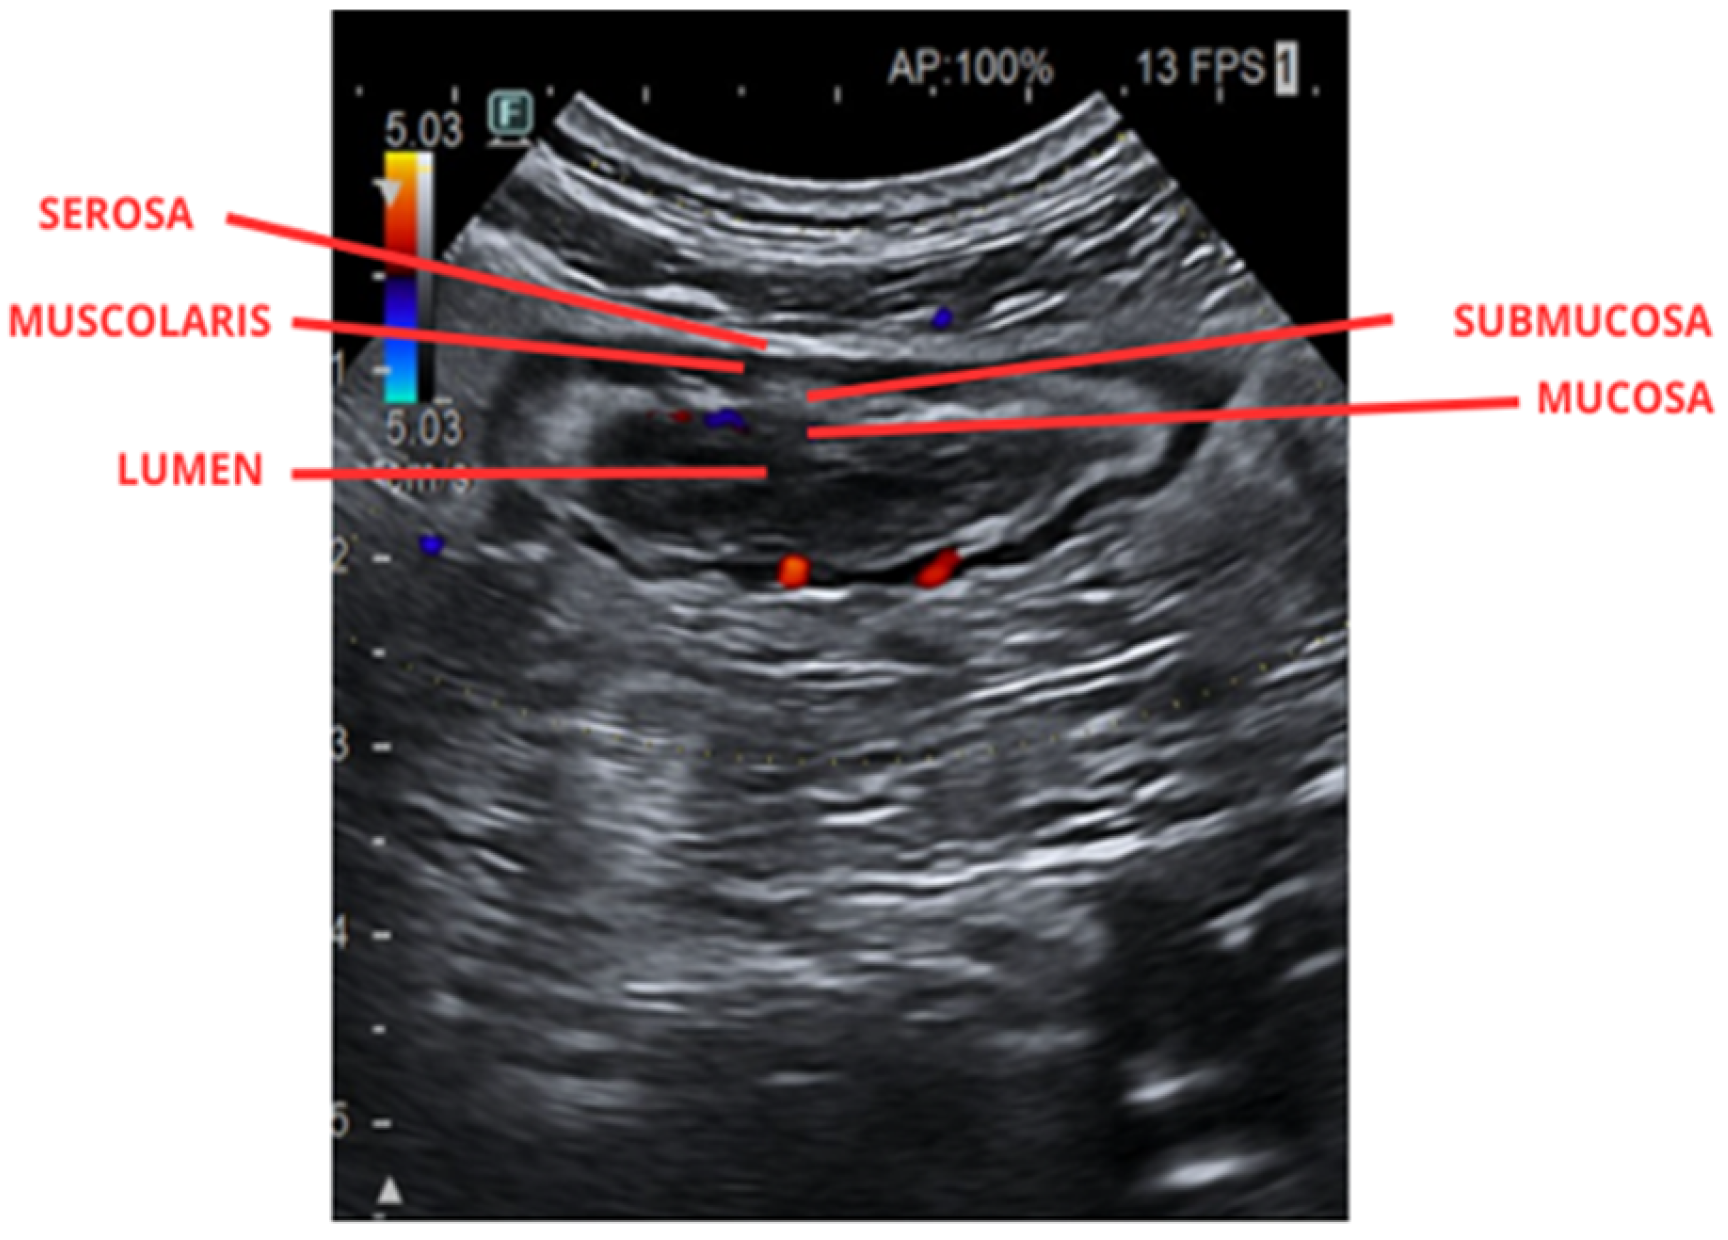

- Atkinson, N.S.S.; Bryant, R.V.; Dong, Y.; Maaser, C.; Kucharzik, T.; Maconi, G.; Asthana, A.K.; Blaivas, M.; Goudie, A.; Gilja, O.H.; et al. How to perform gastrointestinal ultrasound: Anatomy and normal findings. World J. Gastroenterol. 2017, 23, 6931–6941. [Google Scholar] [CrossRef] [PubMed] [PubMed Central]

- Felicani, C.; Trovati, A.; Franchi, E.; Zanni, F.; Verzelloni, F.; Bianchini, A.; Mazzotta, E.; Andreone, P. Transabdominal Gastro-Intestinal UltraSound (GIUS): A visual approach to intestinal pathology. Explor. Dig. Dis. 2024, 3, 241–261. [Google Scholar] [CrossRef]